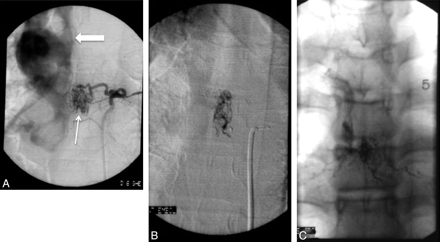

A, A 50-year-old patient with massive SAH (arrow), Hunt and Hess grade IV. B, Reconstructed image from a rotational angiogram shows an aneurysm (arrow) supplied by the ASA. The same arterial feeder supplies a pial AVM (block arrow) distal to the aneurysm. There is duplication of the ASA distally to the branch supplying the aneurysm and pial AVM. C, A Magic 1.2F microcatheter (Balt, Montmorency, France) is advanced over a Mirage 0.08-inch guidewire (ev3) into the ASA branch feeding the aneurysm and the pial AVM. D, Superselective angiography, with the microcatheter into the sulcal branch of the ASA, shows the aneurysm, the pial AVM, and the abnormal venous drainage of the pial AVM (arrows). E, The aneurysm and AVM are embolized with n-BCA, and the glue cast is shown on reformatted 3D CT images (arrow). The patient was temporarily weaker after the procedure, but motor function returned to baseline within a few days.